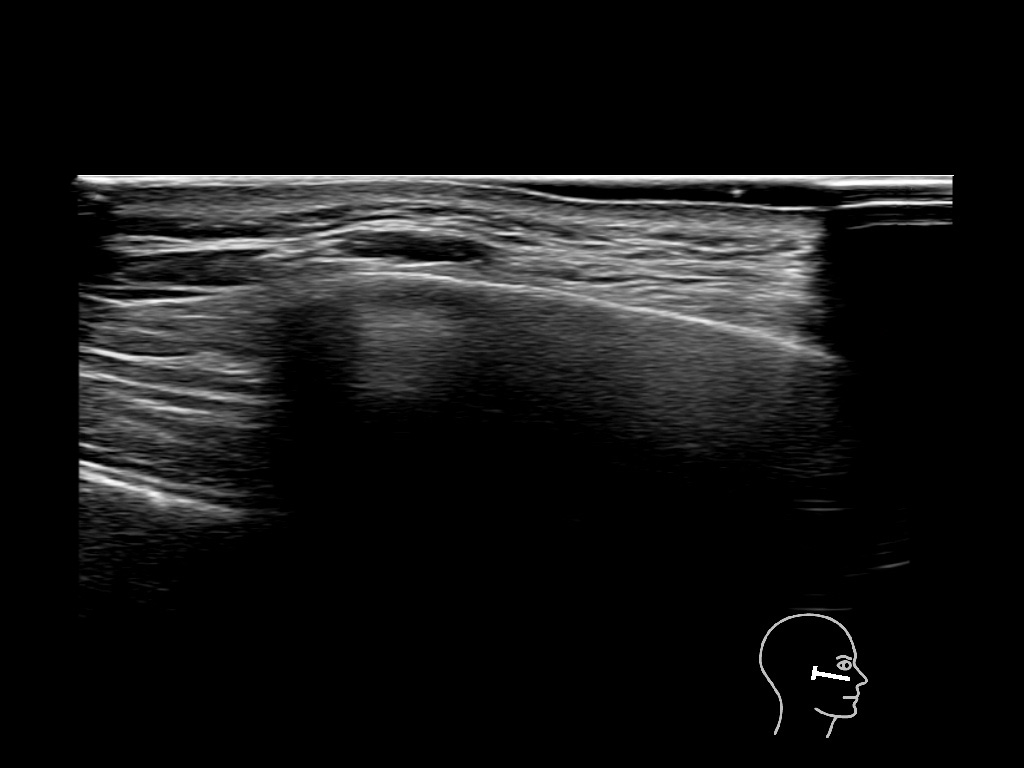

Filler behavior - Temple zygoma US

Study the first image to recognize the different layers. If you are sure about the layers, swipe to the second image to view the answer (if applicable).